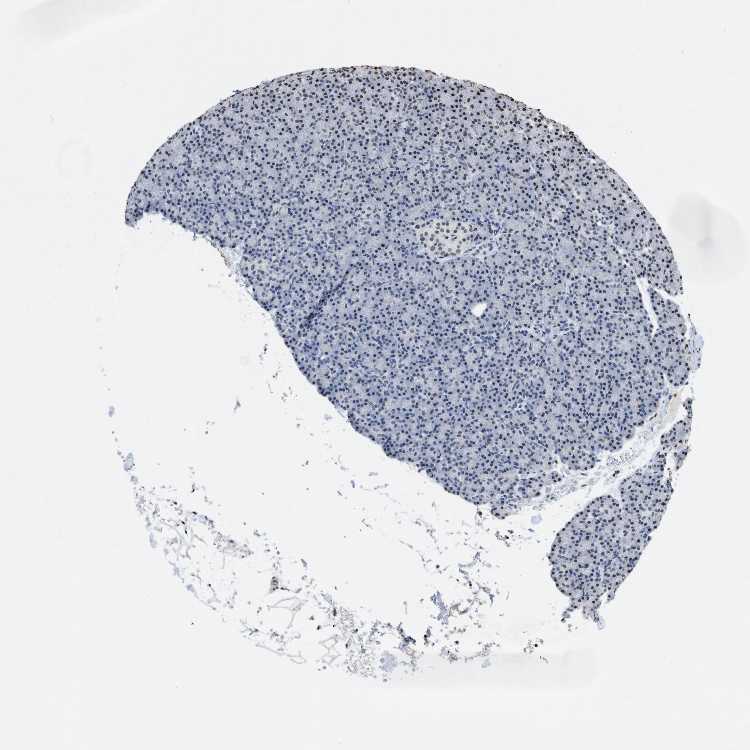

TISSUE PRIMARY DATA PANCREAS Show tissue menu

PANCREAS - Antibody stainingi

Antibody staining in the annotated cell types in the current human tissue is reported as not detected, low, medium, or high, based on conventional immunohistochemistry profiling in selected tissues. This score is based on the combination of the staining intensity and fraction of stained cells.

Each image is clickable and will lead to virtual microscopy that enables deeper exploration of all samples and also displays staining intensity scores, fraction scores and subcellular localization as well as patient and tissue information for each sample.

Antibody HPA021816Antibody CAB002209

Exocrine glandular cells MediumNot detected

Pancreatic endocrine cells LowMedium